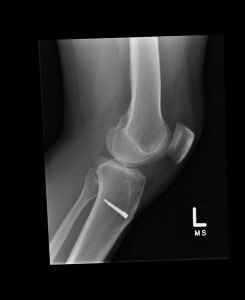

It is also against the law to share patient information inappropriately per federal regulations. If you violate HIPAA confidentiality laws by posting patient imagery online, you might find yourself fired or without your medical license. Congress signed into legislation the Health Insurance Portability and Accountability Act in 1996. We call it HIPAA, and it was enacted to protect patient confidentiality. Protection includes securing and ensuring all electronic patient information – anything electronic discussing a patient, including his or her patient files, medical professional emails, and electronic imagery. Simply put, you can't post a patient's diagnostic imagery on your Facebook page, even if you are doing so to aid other medical professionals with their diagnoses.

What might seem like a good idea could turn out to be a HIPAA violation, as one doctor in Rhode Island found out. Even if you post a medically related picture without the accompanying patient information, those who know the patient might still figure out who the person is. It might seem helpful to post the details of a successful diagnosis and related treatment on your social networking page, but it most likely is not. If anyone figures out that the before and after x-rays belonged to so-and-so, you've violated HIPAA laws, and considering many patients are “friending” their medical professional's social networking pages, the patient him or herself might know you've posted a picture of them on your page. It's better to avoid posting anything medically related online. That way, you are not faced with determining yourself what is right and what is wrong when it comes to your patient's confidentiality.